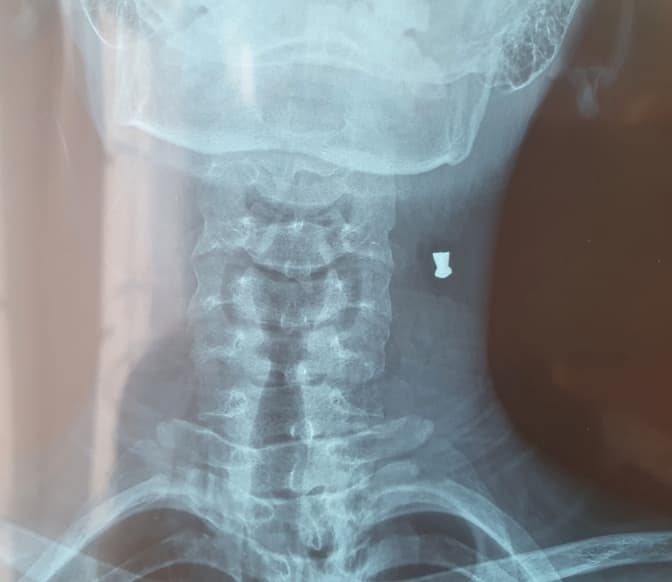

У Львівську обласну дитячу клінічну лікарню ОХМАТДИТ із вогнепальним пораненням потрапив 14-річний хлопець, мешканець одного з районів Львівської області, в якого випадково вистрілив зі зброї брат. Дитина знаходиться на лікуванні, стан у нього стабільний. Про це Тvoemisto.tv повідомили у лікарні ОХМАТДИТ.

«Унаслідок легковажного ставлення дорослих до зброї вдома один із синів, граючись батьковою зброєю, здійснив вогнепальне поранення 14-річній дитині. Куля потрапила у шию. На щастя, обійшлося ураженням м’яких тканин, кулю успішно вилучили», – кажуть у лікарні.

Зараз стан 14-річного хлопця, якому куля потрапила у шию, стабільний.